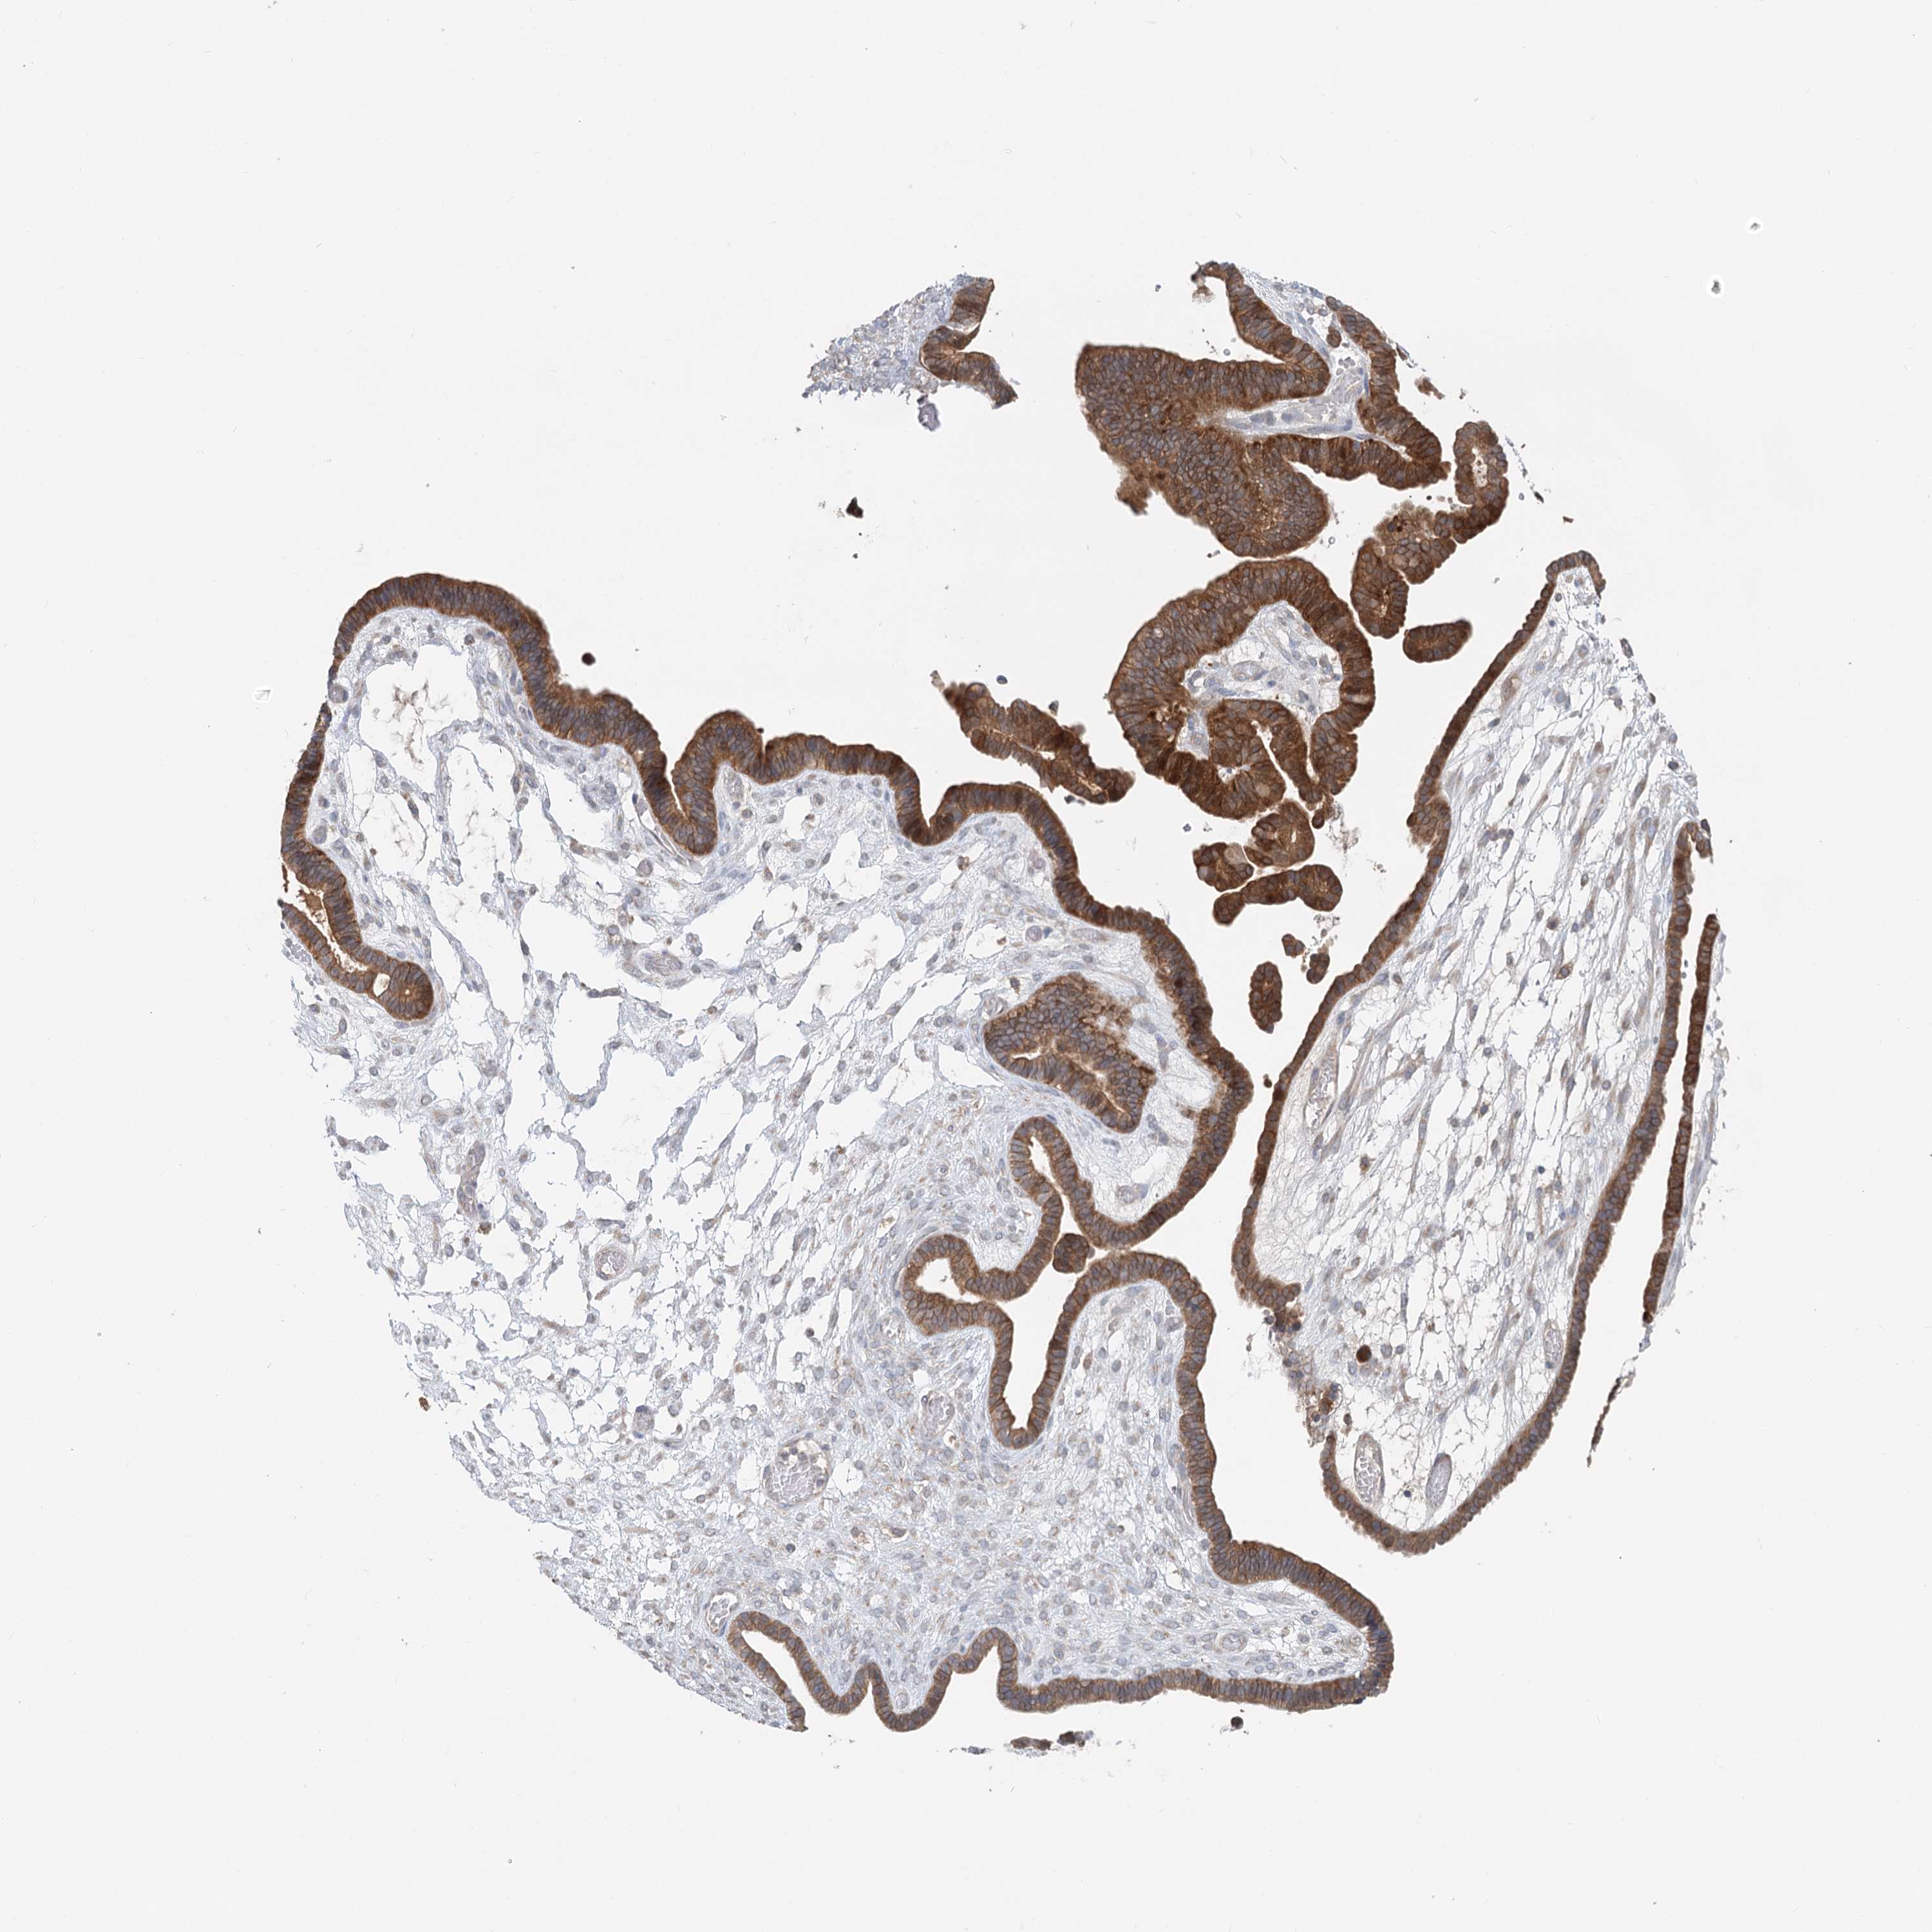

OVARIAN CANCER - Protein expressioni

A mouse-over function shows sample information and annotation data. Click on an image to view it in a full screen mode. Samples can be filtered based on level of antibody staining by selecting one or several of the following categories: high, medium, low and not detected. The assay and annotation is described here.

Note that samples used for immunohistochemistry by the Human Protein Atlas do not correspond to samples in the TCGA dataset.

Antibody stainingi

Antibody staining in the annotated cell types in the current human tissue is reported as not detected, low, medium, or high, based on conventional immunohistochemistry profiling in selected tissues. This score is based on the combination of the staining intensity and fraction of stained cells.

Each image is clickable and will lead to virtual microscopy that enables deeper exploration of all samples and also displays staining intensity scores, fraction scores and subcellular localization as well as patient and tissue information for each sample.

Antibody HPA035945

Antibody HPA056766

Antibody CAB037212

Cystadenocarcinoma, serous, NOS

Carcinoma, endometroid

Cystadenocarcinoma, mucinous, NOS

Carcinoma, NOS